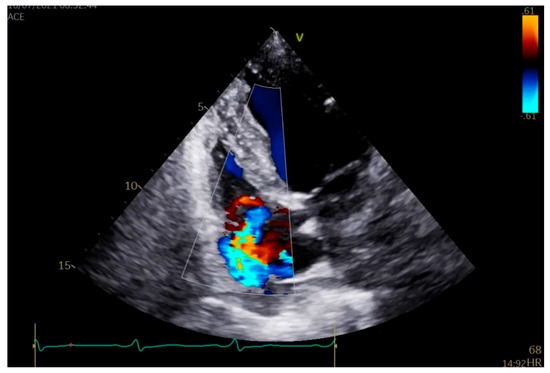

2. Case Presentation